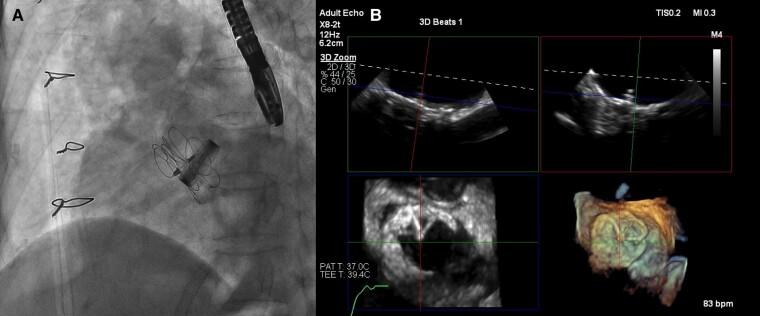

A 68-year-old female was referred to our hospital due to progressive pulmonary artery dilatation observed on her chest X-ray. Echocardiography revealed a secundum ASD with right ventricular dilatation. She had undergone aortic root replacement and aortic valve replacement for annuloaortic ectasia and aortic insufficiency 12 years prior to the diagnosis. She was also diagnosed with Marfan syndrome, which was supported by family histories. Computed tomography did not show a secundum ASD before the surgery. We finally closed the secundum ASD with catheter closure device.

一名68岁女性因胸部X线检查发现肺动脉进行性扩张而转诊至我院。超声心动图显示继发孔型ASD伴右心室扩张。她在诊断前12年因主动脉根部扩张和主动脉瓣关闭不全接受了主动脉根部置换和主动脉瓣置换术。她还被诊断出患有马凡综合征,家族史支持这一诊断。术前计算机断层扫描未显示继发孔型ASD。我们最终使用导管封堵装置闭合了继发孔型ASD。